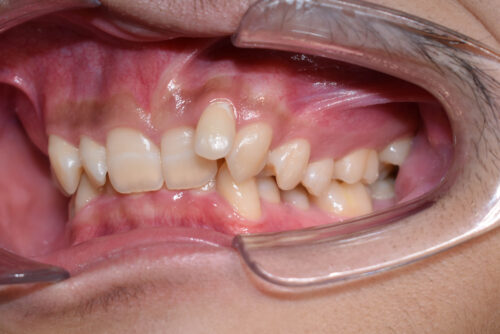

初診時年齢 17歳 男性

歯のでこぼこ (叢生)と

咬み合わせの深さ (過蓋咬合)を

歯のがたつき(叢生)が強く認められ

また下の歯が 全く見えず 過蓋咬合の状態でした。

ワイヤー矯正治療 8か月後です。